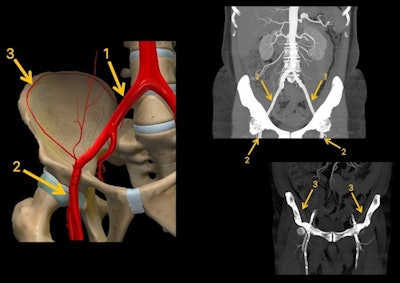

The aim of the exhibit -- called "Bloody hell: Who is the bleeder?" -- was to give easy tips to determine on CT the most probable bleeding artery in pelvic hemorrhages based on a map that shows an approximation of the zonal pelvic vascularization.

"In active bleeds, determining whether the bleeding is arterial (high pressure bleeding) or venous (low pressure bleeding) is important," they pointed out. "Once we have identified there is an arterial active bleeding and we have determined its location, knowing the zonal pelvic vascularization map can help us determine the most probable bleeding artery."

The common iliac artery bifurcates into the internal and the external iliac arteries, the authors wrote. After traveling under the inguinal ligament, the external iliac artery becomes the common femoral artery. The external iliac artery gives off two branches: the inferior epigastric artery and the deep circumflex iliac artery, and the latter supplies the muscles of the anterolateral abdominal wall.

In the internal iliac artery, it is essential to keep aware of the anterior trunk, particularly the obturator artery (which supplies the external obturator muscle and the hip adductors), the inferior gluteal artery (which supplies gluteus maximus, piriformis, internal obturator, superior and inferior gemelli, and quadratus femoris muscles), and the internal pudendal artery (which supplies the muscles of anal and urogenital region), they added.

In the posterior trunk of the internal iliac artery, the following are important: the iliolumbar artery (which supplies psoas major, quadratus lumborum and iliacus muscles), lateral sacral artery (which supplies the erector spinae and piriformis muscles, and the sacrum), and the superior gluteal artery (which supplies piriformis, internal obturator, gluteus maximus, medius and minimus, and tensor fasciae latae muscles).